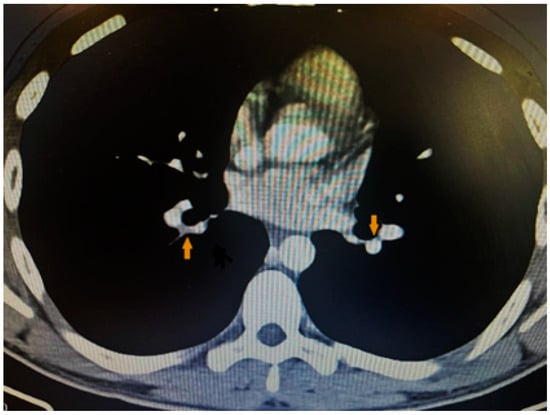

Considering the patient’s complaints of shortness of breath, the ECG changes, and the elevated D-dimer levels, as well as the suspicion of pulmonary embolism, we performed contrast computed tomography, which revealed inhomogeneity and a defect in the filling of small distal branches of the pulmonary artery—more to the left—which confirmed the diagnosis (Figure 3).

Figure 3.

CT showing filling defects within the pulmonary vasculature with acute pulmonary emboli.